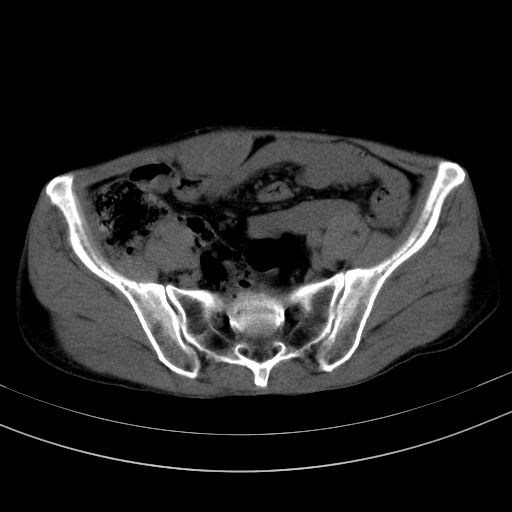

以下是引用37度在2010-1-9 14:37:00的发言:[br]1.双肾囊肿,左肾积水结石,.胆总管轻度扩张;[br]2.病灶在腹膜外,考虑纤维瘤。

以下是引用dyqct在2010-1-9 17:56:00的发言:[br]考虑:1.双肾囊肿,左肾积水结石、旋转不良。[br] 2.右侧腹直肌血肿或纤维瘤。[br]肠道准备不好。做个增强。